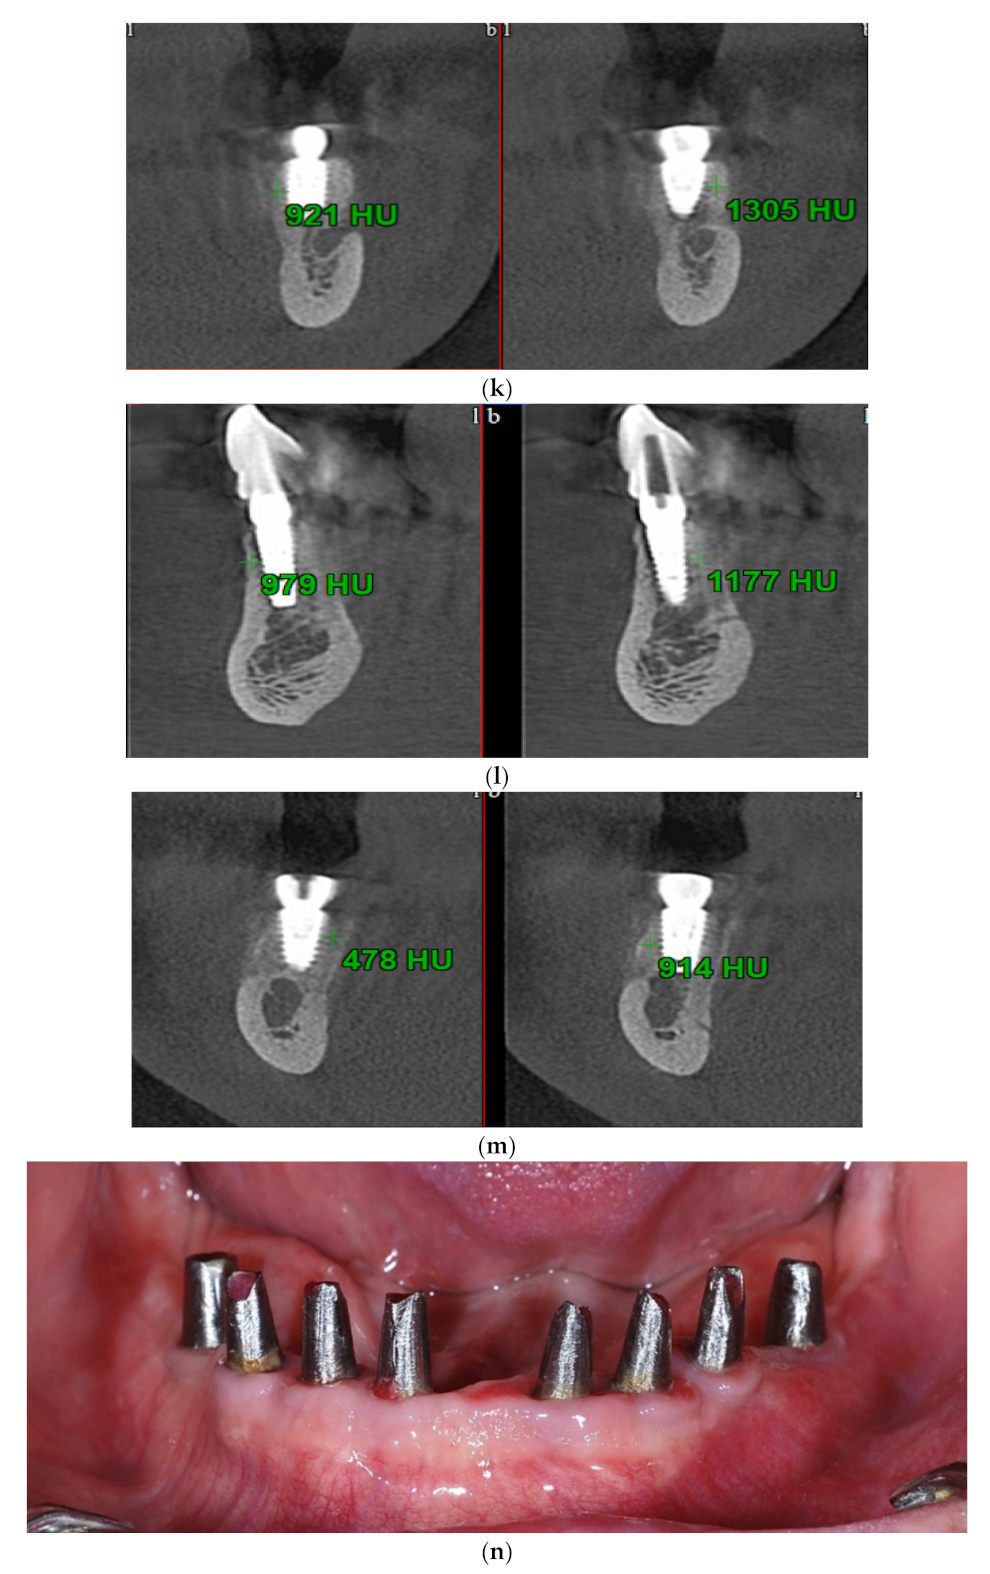

Intraoral view aspects and CBCT images of the implant sites, from a patient included in the test group, are presented in Figure 1a–o (reconstruction of the implant sites by S-GBR technique with porcine-derived xenograft material).

Figure 1.

(a) A.C., aged 65. Preoperatory intraoral view. (b) Preoperative CBCT images and alveolar bone parameters measured with Sidexis XG/ DVT (Densply/Sirona) software. (c) Intraoral view after the insertion of osteosynthesis screws and implants. (d) Intraoral view after the mandibular alveolar reconstruction with S-GBR technique and porcine xenograft. (e) Postoperative intraoral view after wound suture and temporary loading. (f) Alveolar bone width values measured at baseline (left) and at 6 months follow-up with Sidexis XG/ DVT software (Densply/Sirona). (g) Alveolar bone width values measured at baseline (left) and at 6 months follow-up with Sidexis XG/ DVT software (Densply/Sirona). (h) Alveolar bone width values measured at baseline (left) and at 6 months follow-up with Sidexis XG/ DVT software (Densply/Sirona). (i) Alveolar bone width values measured at baseline (left) and at 6 months follow-up with Sidexis XG/DVT software (Densply/Sirona). (j) Alveolar bone osteodensity values measured at baseline (left) and at 6 months follow-up (right) (implant site 4.1). (k) Alveolar bone osteodensity values measured at baseline (left) and at 6 months follow-up (right) (implant site 4.5). (l) Alveolar bone osteodensity values measured at baseline (left) and at 6 months follow-up (right) (implant site 3.2). (m) Alveolar bone osteodensity values measured at baseline (left) and at 6 months follow-up (right) (implant site 3.5). (n) Preloading intraoral view. (o) Postloading intraoral view.